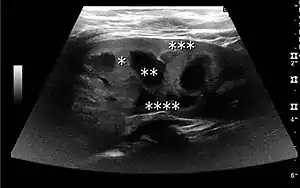

One of the primary indications for referral to US evaluation of the kidneys is evaluation of the urinary collecting system. Enlargement of the urinary collecting system is usually related to urinary obstruction and can include the pelvis, the calyces and the ureter. Hydronephrosis is seen as an anechoic fluid-filled interconnected space with enhancement within the renal sinus, and normally, the dilated pelvis can be differentiated from the dilated calyces.[1]

Several conditions can result in urinary obstruction. In both adults and children, masses, such as abscesses and tumors, can compress the ureter. In children, hydronephrosis can be caused by ureteropelvic junction obstruction, ectopic inserted ureter, primary megaureter and posterior urethral valve (Figure 13). In the latter, both kidneys will be affected. In adults, hydronephrosis can be caused by urolithiasis, obstructing the outlet of the renal pelvis or the ureter, and compression of the ureter from, e.g., pregnancy and retroperitoneal fibrosis. Urolithiasis is the most common cause of hydronephrosis in the adult patient and has a prevalence of 10%–15%.[1]

The hydronephrosis is typically graded visually and can be divided into five categories going from a slight expansion of the renal pelvis to end-stage hydronephrosis with cortical thinning (Figure 15). The evaluation of hydronephrosis can also include measures of calyces at the level of the neck in the longitudinal scan plane, of the dilated renal pelvis in the transverse scan plane and the cortical thickness, as explained previously (Figure 16 and Figure 17).[1]

If the fluid in the dilated collecting system has echoes, pyonephrosis should be excluded by clinical exam, blood analysis and, in special cases, puncture or drainage. Hydronephrosis can also be caused by non-obstructive conditions, such as brisk diuresis in patients treated with diuretics, in pregnant women and in children with vesicoureteral reflux.[1]

Figure 15. End-stage hydronephrosis with cortical thinning. Measurement of pelvic dilatation on the US image is illustrated by ‘+’ and a dashed line.[1]

Figure 16. Hydronephrosis with dilated anechoic pelvis and calyces, along with cortical atrophy. The width of a calyx is measured on the US image in the longitudinal scan plane, and illustrated by ‘+’ and a dashed line.[1]

Figure 17. Same patient as in Figure 16 with measurement of the pelvis dilation in the transverse scan plane illustrated on the US image with ‘+’ and a dashed line.[1]